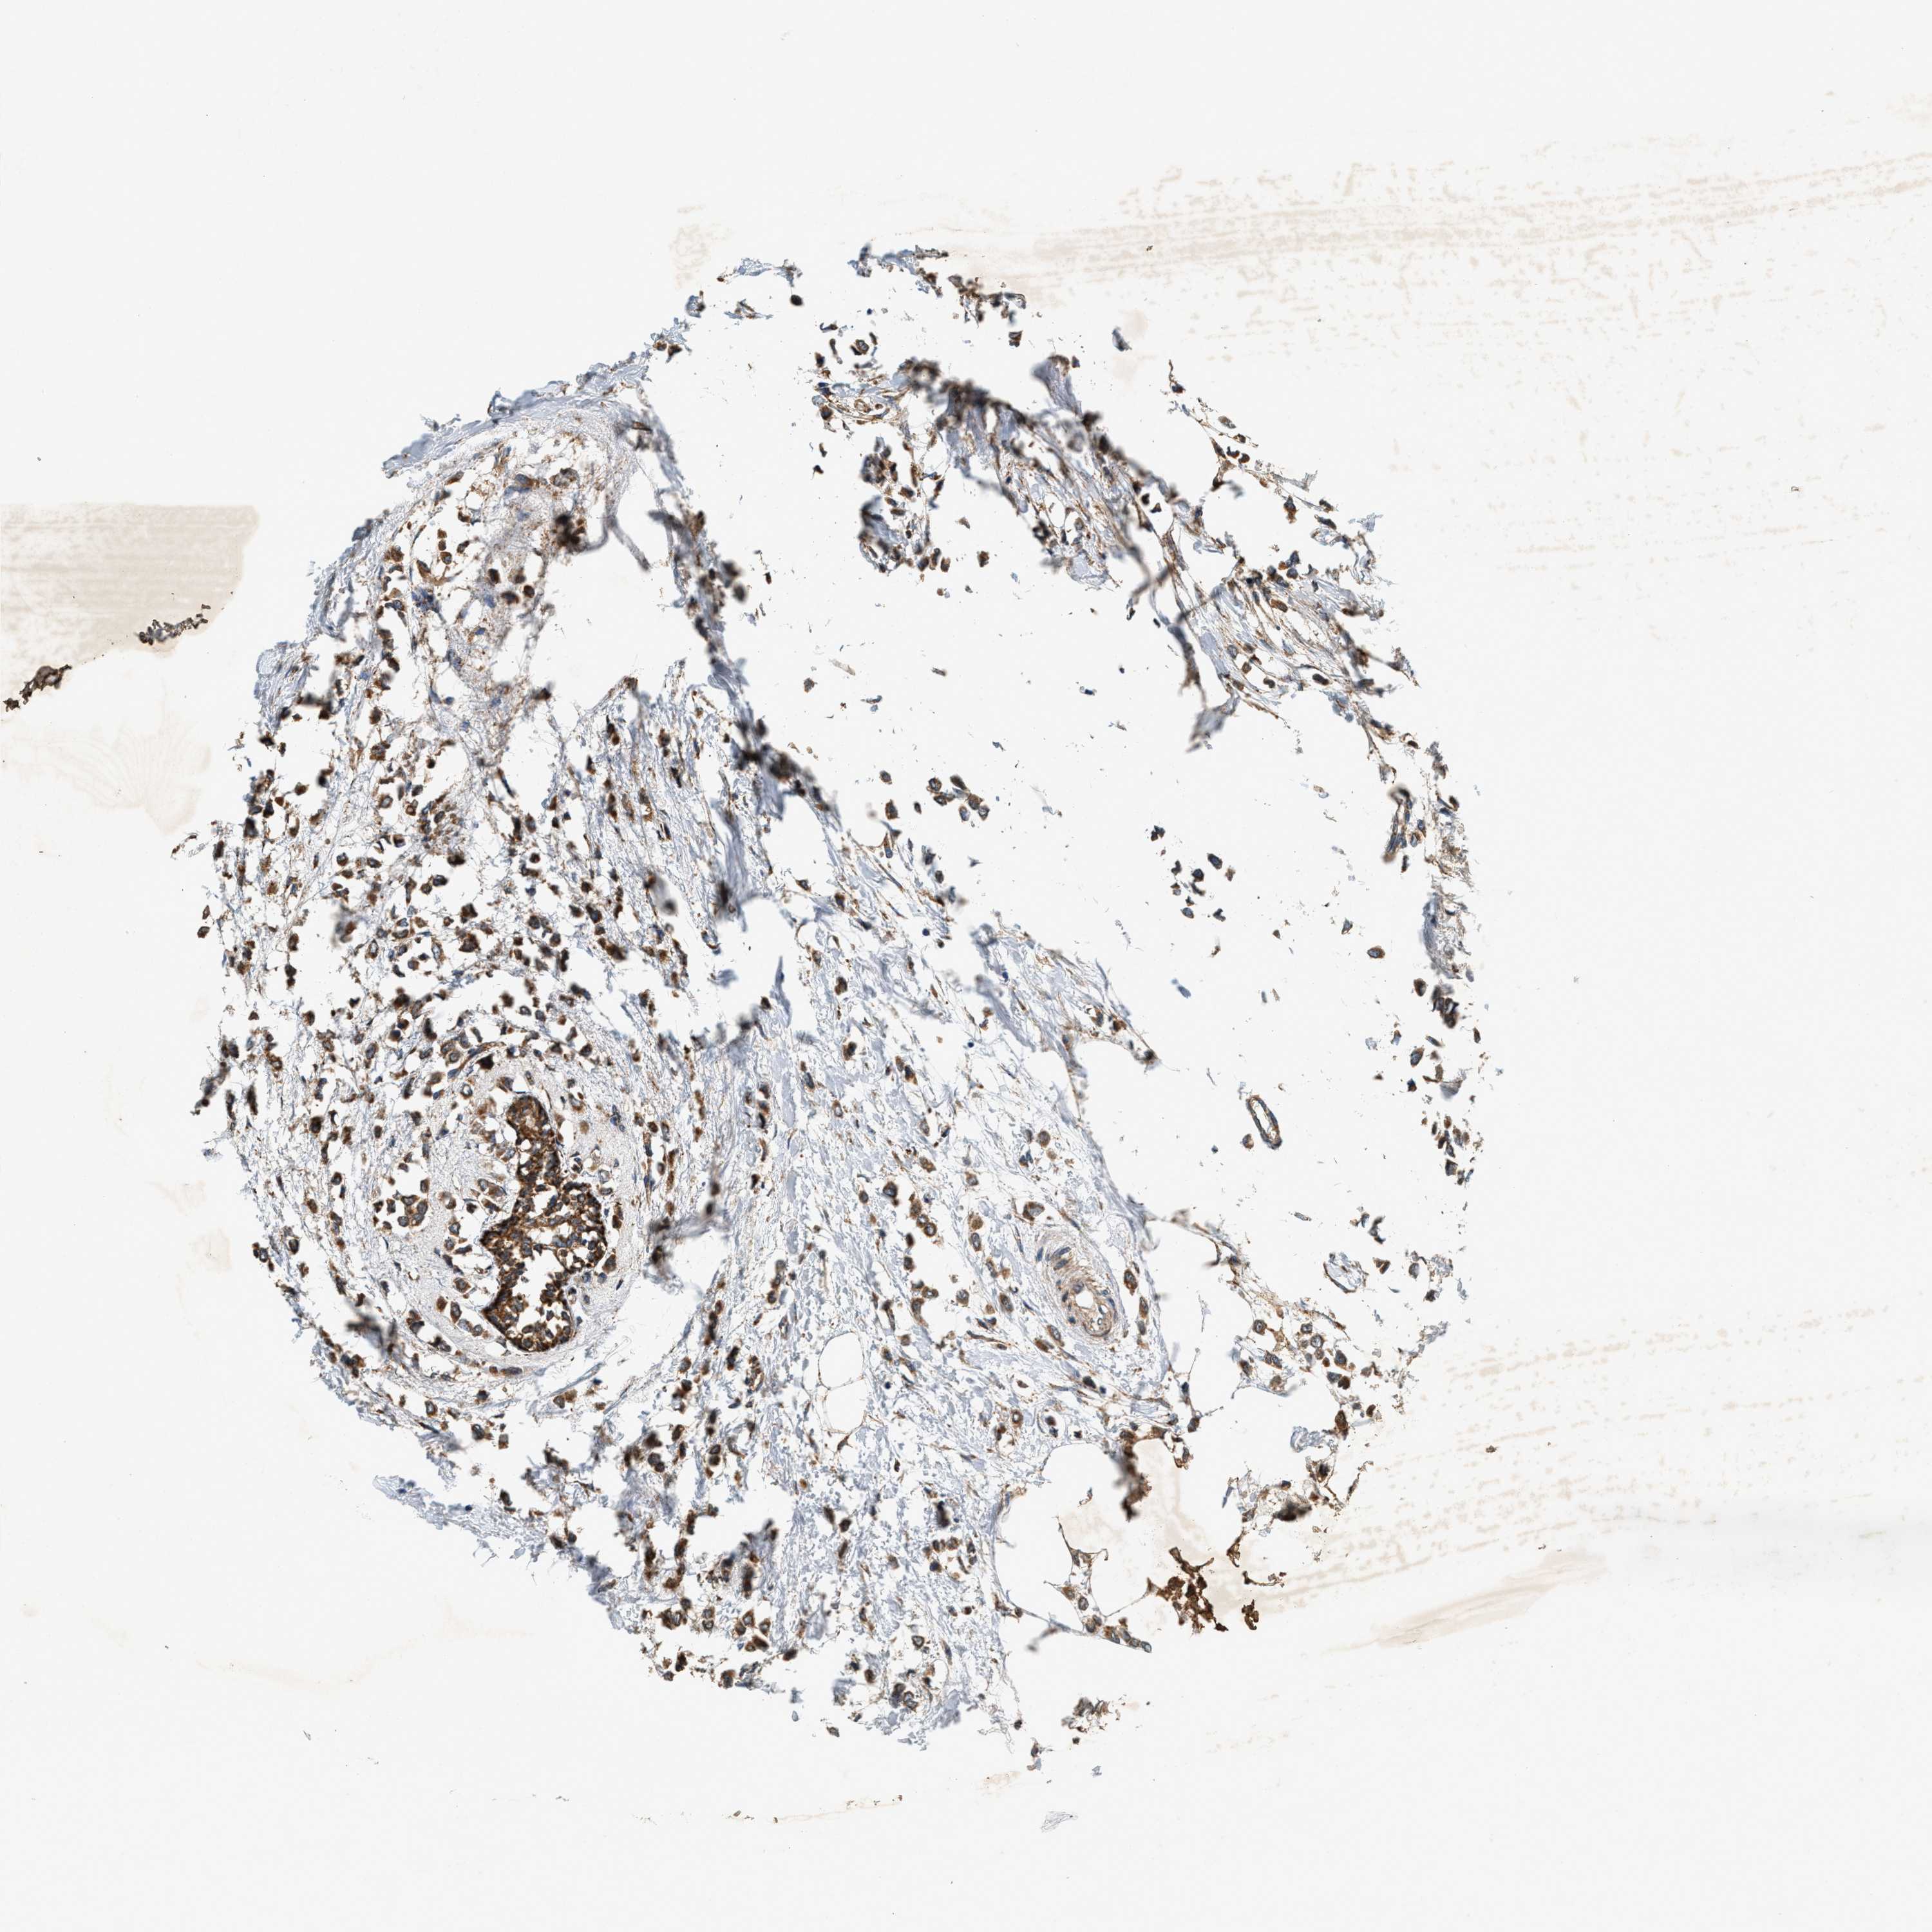

CANCER BREAST CANCER Show tissue menu

BRCA TCGA BRCA VALIDATION PROTEIN EXPRESSION